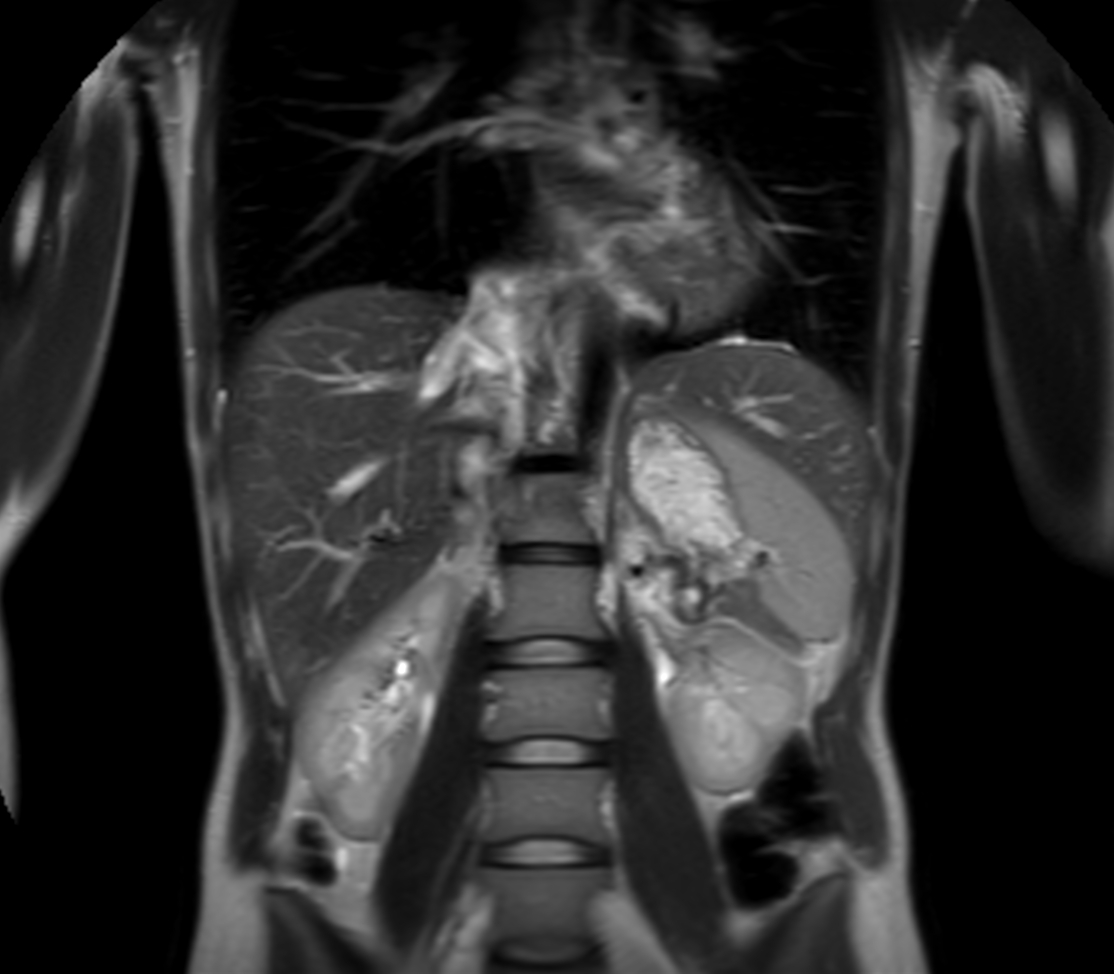

Coronal T2w TSE